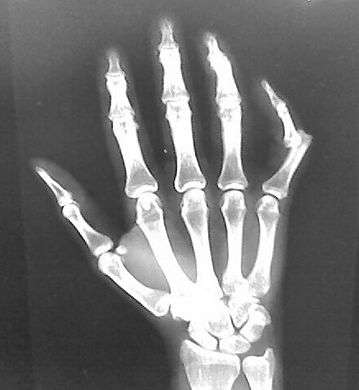

Depiction of reduction of a dislocated spine, ca. 1300- Dislocation of the carpo-metacarpal joint.

X-rays are usually taken to confirm a diagnosis and detect any fractures which may also have occurred at the time of dislocation. A dislocation is easily seen on an X-ray.[8]